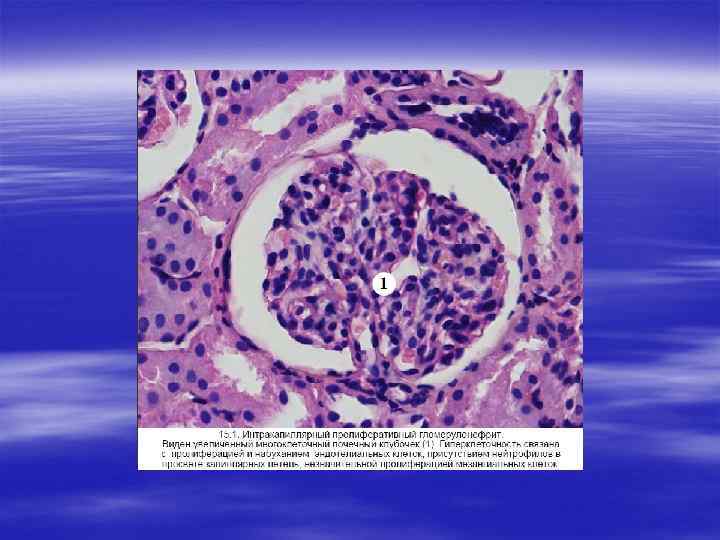

ДИФФУЗНЫЙ ПРОЛИФЕРАТИВНЫЙ ГЛОМЕРУЛОНЕФРИТ Этот вид гломерулонефрита, называемый также § Этот вид гломерулонефрита, называемый также острым гломерулонефритом, представляет собой диффузный воспалитель ный процесс иммунной природы, вызываемый антигенами эндо генного и экзогенного происхождения. § Этиология и патогенез. § Эндогенные антигены формируются при системной красной волчанке. К экзогенным антигенам относятся: § бета гемолитический стрептококк группы А типа 1, 4; § стафилококк, § вирусы инфекционного мононуклеоза, § ветряной оспы, § гепатита В, кори, паротита, вирус Коксаки.

НЕФРИТИЧЕСКИЙ СИНДРОМ § Нефритический синдром характеризуется гематурией, олигурией, азотемией, гипертензией. § Структурной основой нефритического синдрома является воспалительная пролиферация клеток гломерул, сопровождаемая лейкоцитарной инфильтрацией. Развивающаяся воспалительная реакция: § 1) повреждает стенки капилляров, что способствует прохождению эритроцитов и появлению их в моче; § 2) индуцирует гемодинамические нарушения, что ведет к редукции скорости клубочковой фильтрации.

§ Острый нефритический синдром может возникать при си стемных заболеваниях (например, при системной красной волчан ке) или развиваться вследствие первичного поражения клубочков (в частности, при остром диффузном пролиферативном гломерулонефрите).